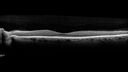

Pseudophakic cystoid macular edema (CME)158 views66 year old female 4 months following cataract surgery. Never had very good vision after surgery. On PF QID for one month. VA 20/50 in both eyes.